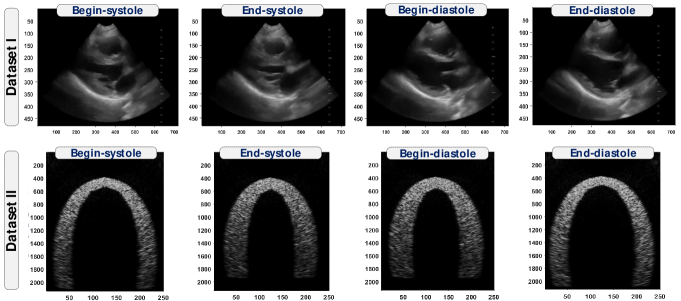

We used two ultrafast ultrasound datasets (see Figure 5) to evaluate our proposed approach.

The first is a realistic dataset from one patient. During the acquisition, the patient was placed in the supine position or left lateral decubitus. Then, the probe was placed on the left parasternal line at the fourth intercostal space with the marker pointing toward the right shoulder of the patient. The images were thus taken from the parasternal long axis view. This view is useful for global assessment of the motion of the heart’s wall and the function of different areas including the right and left ventricle, the mitral and aortic valves and the interventricular septum. This dataset is composed of frames with size of x, and a scaled version of size x. This data was acquired with an UUS device with a (fc) transducer with a bandwidth of 6MHz and 192 elements using coherent compounding of plane waves. The output is a 2D plane wave image sequence of the long axis view of a healthy heart.

The second dataset (see [19] for details) is a simulated ultrafast ultrasound sequence that has a realistic cardiac deformation field and describes the mechanics of a healthy left ventricle (see [55] for the description of the mechanics). This data was generated using (fc) transducer with a frame rate of 5000 Hz (single transmits) and effective frame rate of 500 Hz. The output of this simulated data is a set of 2D apical imaging planes. This view is helpful to study the left ventricle and the mitral inflow. The sequence is composed of frames with size of x. This simulated data is very helpful to assess the performance of our approach since it includes a ground truth of the displacements which can be compared against our estimation.